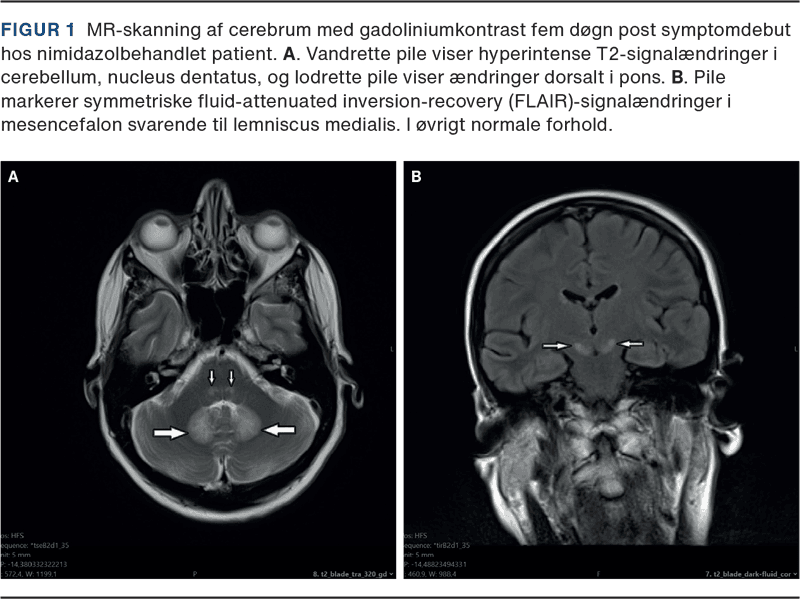

Blodprøver, inkl. paraneoplastiske antistoffer og levertal, var normale og bloddyrkning var uden vækst. Neurofysiologi viste aksonal sensorisk polyneuropati med fravær af sensoriske signaler i n. suralis og n. peroneus bilateralt og nedsat amplitude i venstre n. medianus og n. radialis. Cerebrospinalvæske viste normalt celletal, protein og laktat. BioFire-panel var negativt, herpes simplex-virus- og varicella-zoster-virus-intratekal test var negativ, og cytologisk cerebrospinalvæskeundersøgelse viste intet malignitetssuspekt. CT af cerebrum med kontrast viste intet abnormt, specielt ingen tegn på intrakraniel indvækst af primærtumor. MR-skanning af cerebrum viste fund som beskrevet i Figur 1 A + B. Et identisk MR-billede er velbeskrevet ved metronidazolinduceret encefalopati.

Baseret på det kliniske billede og radiologiske fund (Figur 1) blev toksisk encefalopati forårsaget af NI vurderet som den mest sandsynlige diagnose, og behandlingen blev seponeret. Alle radiologiske fund remitterede fuldstændigt inden for fire uger efter ophør med NI, bekræftet ved en opfølgende normaliseret MR-skanning af cerebrum. De kliniske centralnervesystem (CNS)-symptomer remitterede i samme periode, hvorimod den perifere neuropati, mere sandsynligt forårsaget af cisplatin end NI, persisterede.